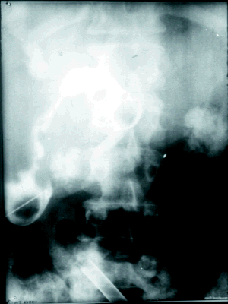

El 15 de noviembre de 1974 se hizo la primera duodenoscopia para cateterismo de vía biliar sin éxito, por tratarse de un adenocarcinoma de vesícula comprobado por laparotomia posterior y el 4 de diciembre del mismo año se practicó el primer cateterismo en una ictericia obstructiva por colecisto-colédocolitiasis (Figura 16) primera que se hacía en Colombia, presentando estas experiencias iniciales el 21 de noviembre en la XXIV Convención Nacional de Gastroenterología y V de Endoscopia Digestiva llevadas a cabo del 19 al 22 de noviembre de 1975 en Montería (Figura 17) bajo el título de "Cateterismo de vía biliar y pancreática por duodenoscopia" (17) (Figura 18) y posteriormente ampliadas en Quito y Cuenca, Ecuador del 20 al 22 de julio de 1977 (18).

Figura 16. Primera CPRE.